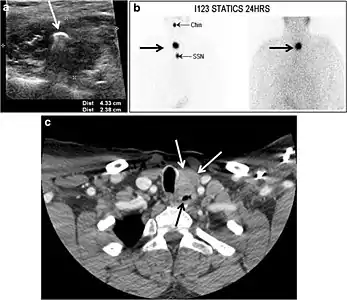

Fig. 7. A 51-year-old female patient post total thyroidectomy for PTC with elevated thyroglobulin measurement. an Axial non-enhanced CT scan of the neck at the level of the thyroid bed demonstrates a well-defined, rounded, homogenously dense soft tissue situated between the trachea and left internal jugular vein (white arrow). b Transverse ultrasound image of the neck demonstrates a well-defined, homogeneous, hypoechoic soft tissue nodule measuring 6 mm (white arrow) with no detected micro-calcifications. Biopsy showed a predominantly residual normal thyroid tissue with micro-foci of PTC.[1]